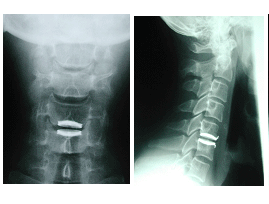

Raio-X de controle pós-operatório : paciente com quadro de mielopatia cervical por espondiloartrose cervical-abordagem via anterior C4-C5/C5-C6/C6-C7

Raios-X = ilustração de artrodese via anterior da coluna cervical com uma placa de metal com parafusos de fixação no corpo vertebral, e enxerto ósseo entre as vértebras enquanto ocorre a fusão. Abaixo um disco intervertebral artificial.